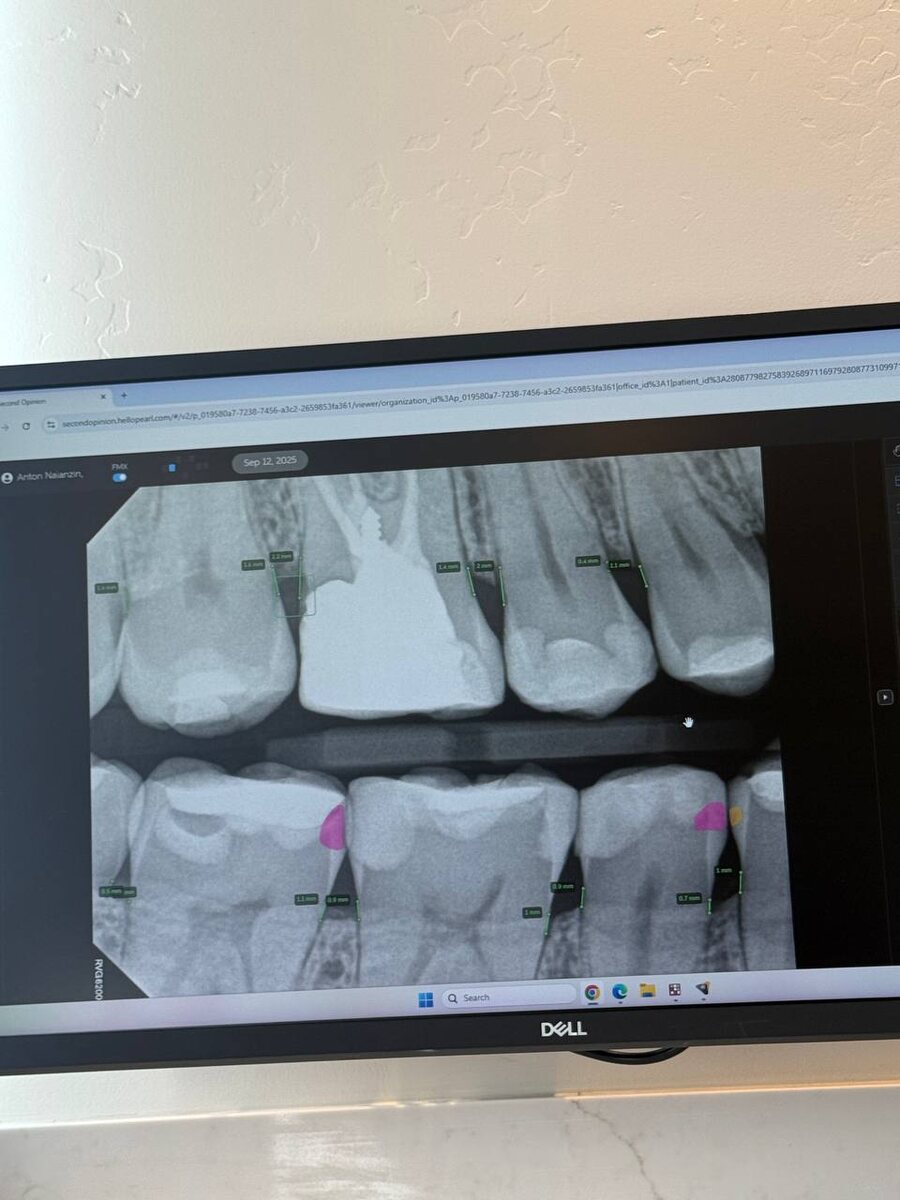

AI уже ворвался в стоматологию США Пришел на плановый осмотр к моему дантисту Ане и был очень удивлен, насколько искусственный интеллект внедрен в работу стоматологической клиники, в которой она работает. Например, на рентген снимке он показывает места, где есть подозрения на кариес, воспалительные процессы, измеряет потерю кости, видит все важные для лечения нюансы. А самое интересное, это всё очень помогает не просто качественно проводить диагностику, но и даже отправлять информацию в страховые компании, которые руководствуются рекомендациям AI.

Например, на рентген снимке он показывает места, где есть подозрения на кариес, воспалительные процессы, измеряет потерю кости, видит все важные для лечения нюансы.

А самое интересное, это всё очень помогает не просто качественно проводить диагностику, но и даже отправлять информацию в страховые компании, которые руководствуются рекомендациям AI.